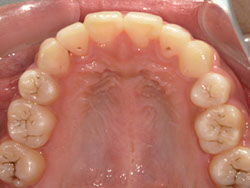

1期治療でスケルトンタイプの拡大装置で歯列拡大後、歯も抜かずにきれいになりました。

矯正終了後